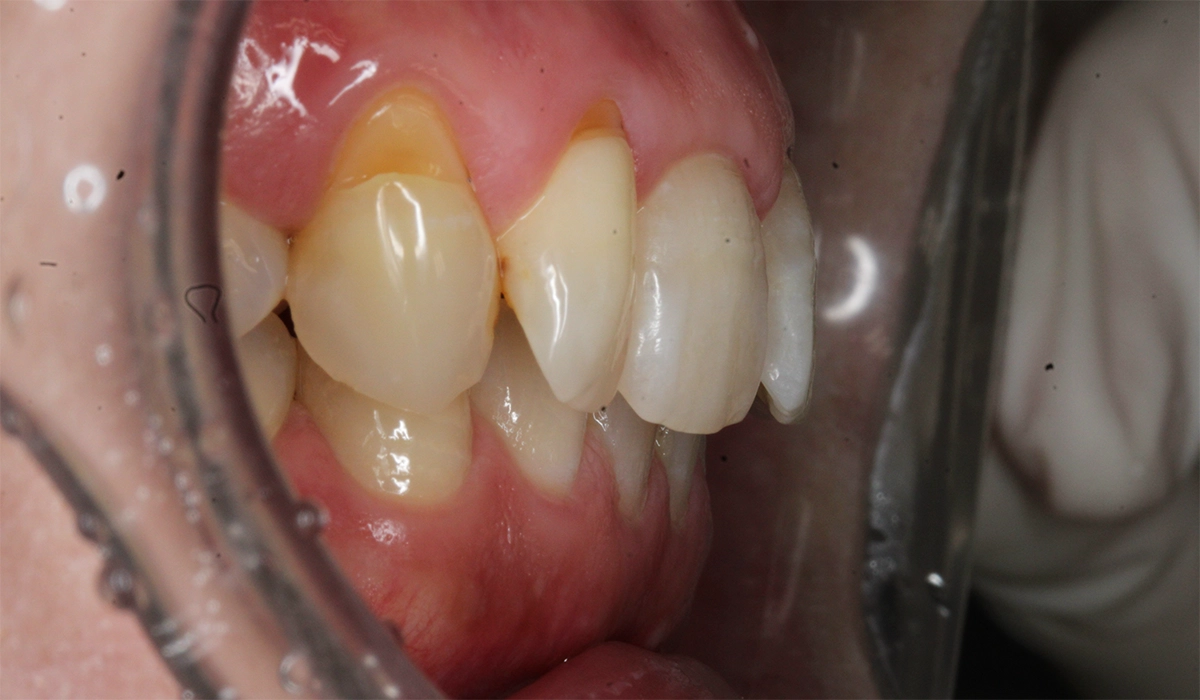

術前:左側